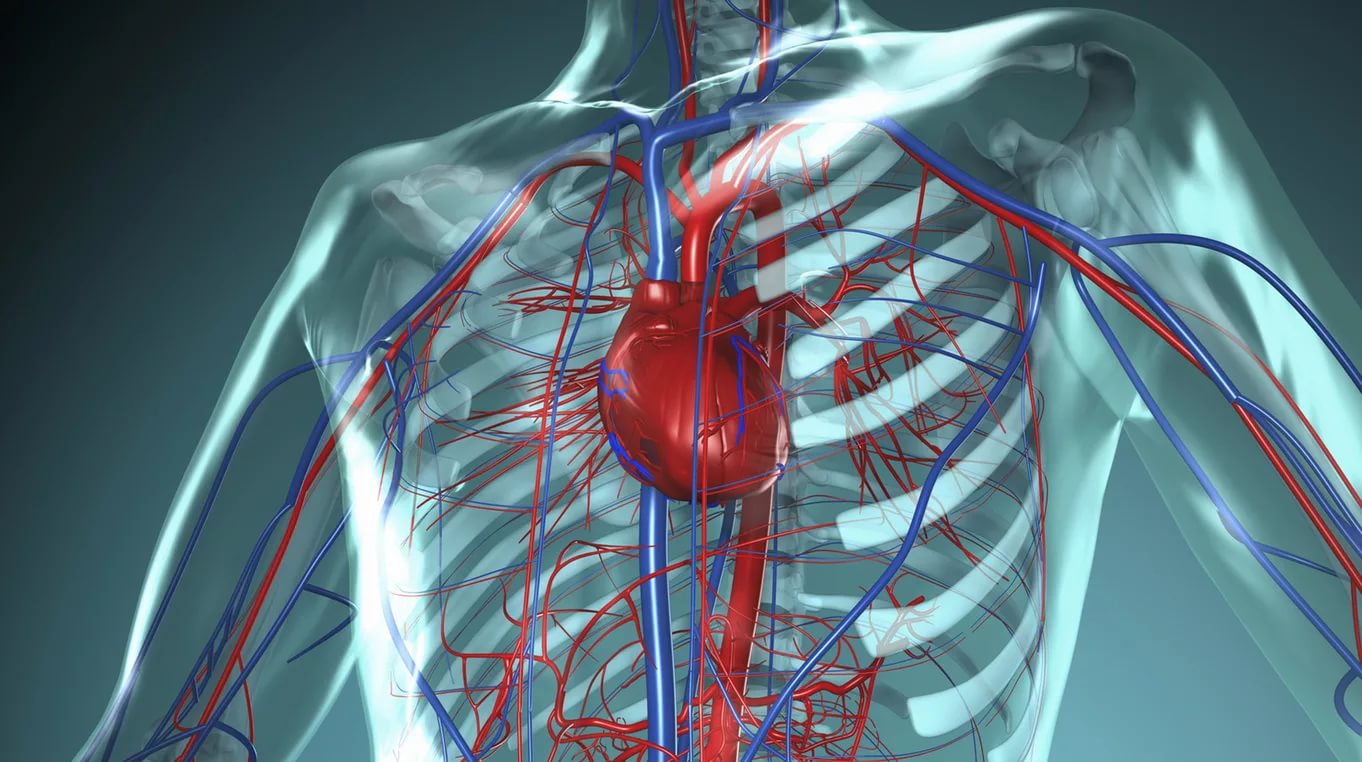

Кровеносная система человека: структура и функции

Раздел: Идеи и советы